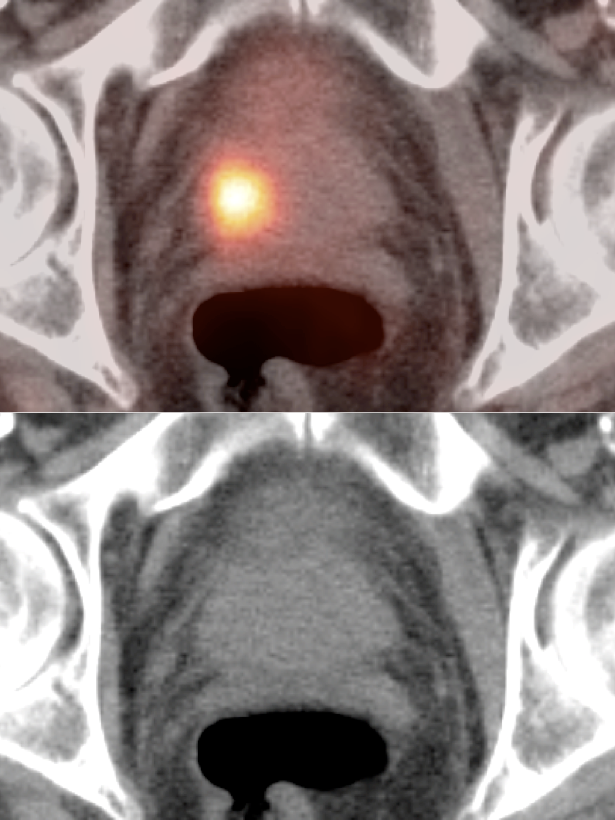

Utility of PET/CT:

- Detection of local recurrence and/or metastatic disease in patients with “PSA Relapse” or “Biochemical Failure”.

- Primary Lesion: Often not identified. When present, usually appears as a focus of intense uptake in the peripheral zone (MRI is superior in the evaluation of the primary lesion).

- Regional Disease: Usually hypermetabolic pelvic lymph nodes.

- Distant Disease: Most commonly to the bones, lymph nodes, lung, liver and brain.